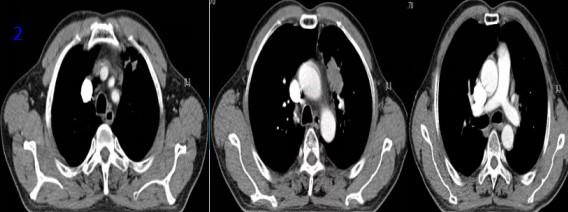

2022年3月15日再程放療后5個月復(fù)查胸部CT可見腫瘤較前縮?。▓D7),RECIST評價PR。

圖7再程放療后胸部CT

2022年10月18日再程放療后12個月復(fù)查胸部CT可見腫瘤較前縮?。▓D8),RECIST評價PR。

圖8再程放療后12個月胸部CT

2023年12月26日再程放療后24個月復(fù)查胸部CT可見腫瘤明顯縮?。▓D9),RECIST評價PR。2024年2月18日、2024年12月22日、2025年4月15日在外院行胸部CT提示“左肺上葉及縱隔旁見斑片條索陰影,考慮增值性病灶”。2025年8月20日電話隨訪,患者正常生活,未訴任何不適?;颊咴俪谭暖熀?年8個月,病情穩(wěn)定,總生存超過5年,達(dá)到臨床治愈效果。

圖9 再程放療后24個月胸部CT